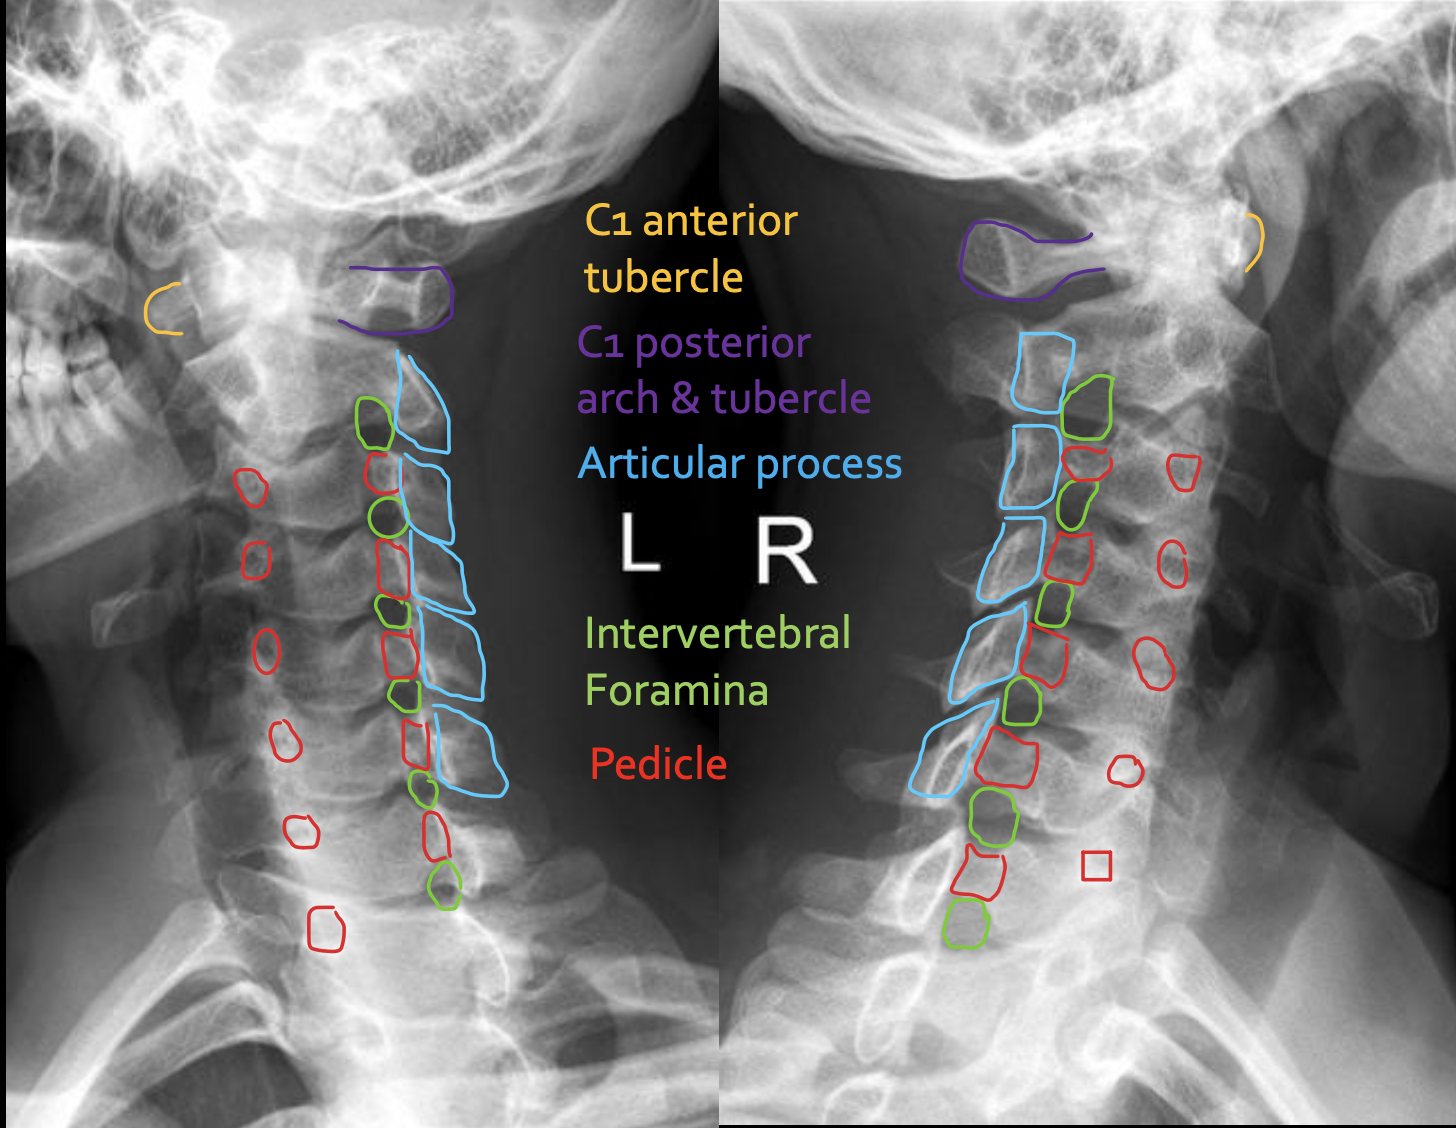

寰椎前结节

C1 anterior tubercle

寰椎后弓及后结节

C1 posterior arch & tubercle

关节突

Articular process

椎间孔

Intervertebral Foramina

椎弓根

Pedicle